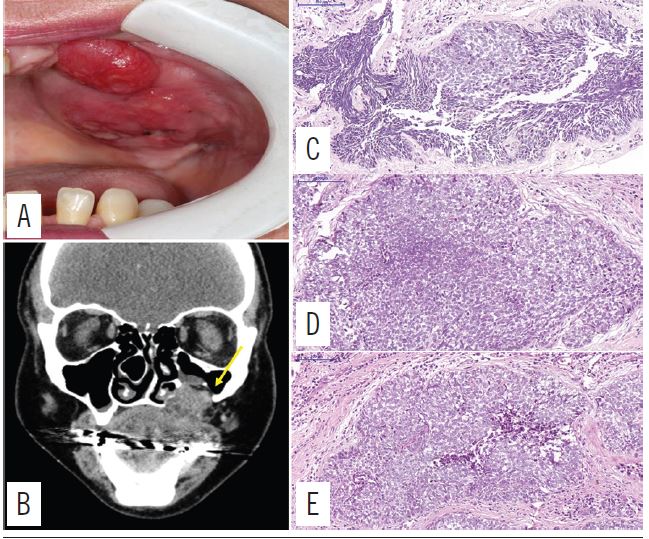

Patient postoperative follow-up occurred at one, three and four weeks after surgery. Only one year after the surgical procedure, the patient returned presenting with a third recurrence. During the clinical examination, an erythematous, tumoral lesion of sessile insertion was observed, covering the entire left hemi-arch, with an irregular, non-delimited surface, ulceration areas and a tumor-like appearance. Histopathologically, fragments of malignant neoplasm of odontogenic epithelial origin, showing cellular atypia and pleomorphism, nuclear hyperchromatism, cystic degeneration foci and necrosis were revealed. The supporting stroma was of a dense fibrovascular connective tissue with slight mononuclear inflammatory infiltrated areas. Focal areas of desmoplasia were also observed (Figure 3).

CT: computed tomography; HE: hematoxylin and eosin.

During an intraoral examination, a lesion was seen in the left maxilla, with an erythematous, tumoral aspect and a sessile insertion, approximately 1 cm long, with a non-delimited irregular surface, displaying ulcerated areas. The imaging tests revealed radiolucency and radiodensity in a panoramic radiograph and computed tomography, respectively, where rupture of the cortical bone and invasion of the maxillary sinus were observed. Therefore, the patient underwent an incisional biopsy, presenting a histopathological report of ameloblastoma (Figure 2).